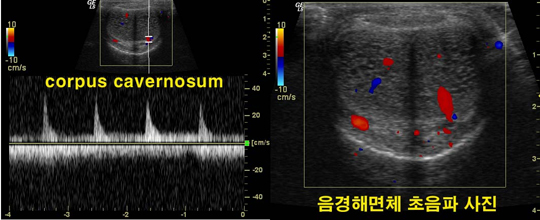

곧고 굳은 대나무는 예로부터 나라를 사랑하는 충심, 변하지 않는 선비의 미덕 등 긍정적인 이미지로 표현되었다. 헌데, 이러한 이미지가 또 필요한 곳이 있다. 바로 남성의 성기이다. 곧고 굳은 남성의 성기는 그야말로 남성스러움, 남성다움을 잘 드러낸다. 하지만, 반대로 흐물흐물하고 휜 남성의 성기는 남성스러움과는 거리가 먼 콤플렉스로 작용하게 된다. 남성의 성기가 휘었다는 것은 어떤 의미일까? 흐물흐물하다는 것은 발기가 되지 않은 상태라고 쉽게 이해할 수 있다. 그렇다면 남성의 성기가 휘었다는 것은 어떤 뜻일까? ✔ 내 성기는 그저 휘었을 뿐이고. 남들과 다를 뿐이고. 여성들은 남성의 성기가 모두 다 같은 모양일 것이라 생각한다. 하지만 그것은 오산이다. 사람의 얼굴이 모두 제각각이듯, 남성의 성기 모양도 사람마다 조금씩 다르다. 조금씩 다른 모양은 얼굴의 개성처럼 별 문제가 되지 않지만, 이렇게 눈으로 봐도 ‘휘어진 정도’가 보이는 경우라면 문제가 있다. 마치, 안면비대칭이 심해서 문제가 되는 경우와 비슷하다고 하면 이해가 쉽겠다. 양쪽 얼굴이 확연하게 비대칭인 안면비대칭이 겉으로 보아도 보기에 좋지 않고, 얼굴의 기능에도 좋지 않은 영향을 미쳐 교정이 필요하듯이, 남성의 성기가 휜 경우도 여러 가지 심미적, 기능적 문제를 일으킨다. 강남J비뇨기과(강남제이비뇨기과) 박천진 원장은 “이렇게 남성의 성기가 휜 증상을 ‘음경만곡증’이라 한다. 바나나 모양처럼 약간 휜 경우에서부터, 낫과 같이 심하게 휜 경우 등 그 정도는 개개인에 따라 다른데, 대체로 전체 환자의 약 75%는 아래쪽으로 휘고, 약 20%정도는 좌우 양쪽으로 휘는 증상을 보인다.” 며 “정도에 따라 ‘바나나’ 나 ‘코브라’ 등으로 묘사되기도 한다.”라 덧붙인다. 그렇다면 음경만곡증은 왜 생기는 것일까? 박천진 원장은 “음경만곡증은 남성의 발기를 돕는 ‘음경해면체’가 선천적으로 좌우 균형이 맞지 않으면서 발생하는 경우와, 과도한 성행위나 자위행위로 인해 발생하는 경우, 노화로 인해 점차 발행하는 경우 등이 있다.”라 전한다. 박천진 원장은 또한 “음경이 발기가 될 때 길어지는 것은 음경내부의 백막으로 인한 것인데, 이것이 과도한 성행위로 부러져 음경골절이 생기면, 그 사이로 살이 채워지면서 음경만곡증이 생길 수 있다. 또한 노화로 인해 이러한 백막이 점차 탄력성을 잃게 되면서 음경만곡증이 생기게 되는 것”라 덧붙인다. ‘보기에 조금 휜 정도일 뿐인데, 기능적으로도 과연 문제가 될까?’ 라고 생각하는 이들도 있을 것이다. 하지만, 실제 음경만곡증이 있는 이들은 심미적 문제보다 기능적 문제를 더 호소한다. 정상적인 성관계가 힘들어 지거나 성기에 통증이 느껴지기 때문이다. 음경이 휜 경우, 성관계 시 상대방 여성에게 상당한 고통을 줄 수 있고, 자신에게도 통증이 생기게 된다. 심할 경우, 발기부전 등의 증상도 나타날 수 있어 조속한 치료가 중요하다. 음경만곡증이라면 반드시 전문의를 찾아 검사를 받고 적절한 치료를 받는 것이 좋겠다. 지속적인 치료 후 호전이 될 수 있는데, 만일 호전이 없다면 수술적인 치료를 받을 수 있다. 수술은 음경내부의 백막 일부를 절개해서 성형하는 성형법이나, 음경이 휘지 않은 쪽 백막을 주름을 잡아서 꿰매주는 주름법 등이 있고, 최근에는 patch를 이용해서 완성도 높은 수술이 가능해졌다고 한다. [OSEN=생활경제팀]osenstar@osen.co.kr 강남J비뇨기과 제공 온라인으로 받아보는 스포츠 신문, 디지털 무가지 OSEN Fun&Fun, 매일 3판 발행